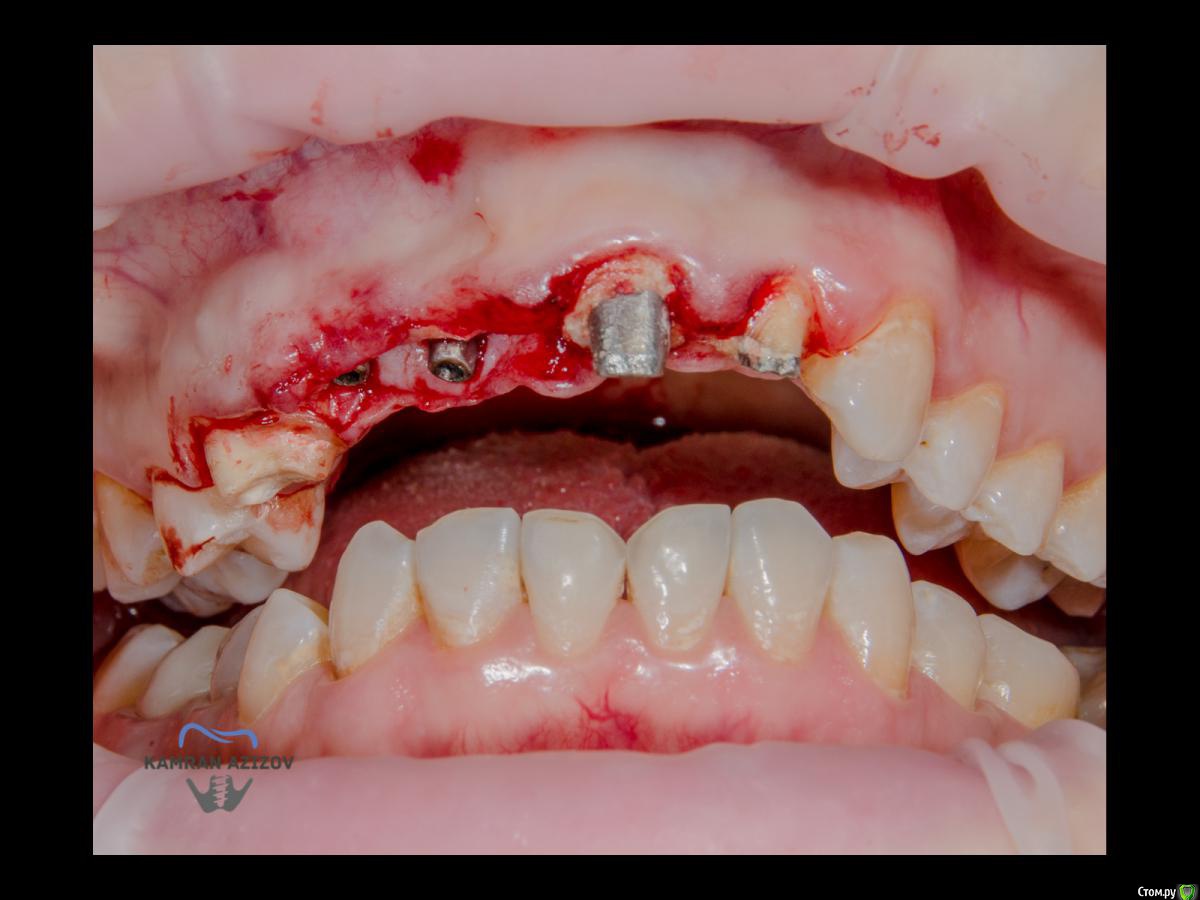

kamranchick Опубликовано 6 апреля, 2019 Поделиться Опубликовано 6 апреля, 2019 (изменено) Хай Гайсдавно ничего не комментировал и не выкладывал, что то настроения не было, да и муза не посещалаСитуация следующаяпришла пациентка, жалобы на неприятный запах из рта, сначала не понял что за хрень, ну как распилил мост понял че к чему... халтура.Ну и по кейсуУдаление клыка и 2ки, через 2 месяца навигация, имплантация + Шашлыки по карлоссу, смена формиков, временное протезирование. только мягкие ткани, Изменено 6 апреля, 2019 пользователем kamranchick 7 1 Ссылка на комментарий

kamranchick Опубликовано 7 апреля, 2019 Автор Поделиться Опубликовано 7 апреля, 2019 Тут все на винтовой фиксации Ссылка на комментарий

kamranchick Опубликовано 8 апреля, 2019 Автор Поделиться Опубликовано 8 апреля, 2019 ТакУважаемый Петр) начнем по порядку1. пациентка отказалась от нее, как только не уговаривал ее, просто танцы с бубном были)2. после удаления клыка сразу ушел хиленький резец, делать мост 14-21-22 как то страшновато было из-за протяженности дефекта3. 1.4 зуб жалко было удалять, зачем удалять еще один зуб если так и так 2 имплантата, ну как вариант можно было бы, было бы легче позиционировать имлпнтататы4. в позиции 1.1 был большой резцовый канал, не захотелось проводить какие то манипуляции вокруг него и с ним, ну как то так)) Ссылка на комментарий

kamranchick Опубликовано 9 апреля, 2019 Автор Поделиться Опубликовано 9 апреля, 2019 kamranchick11з консоль, или это единая конструкция?13-12 с консолью на 11 Ссылка на комментарий

kamranchick Опубликовано 9 апреля, 2019 Автор Поделиться Опубликовано 9 апреля, 2019 Поняно По пункту 4, если формировались лоскуты, почему бы не убрать содержимое резцового канала и не использовать позицию 11з? Ведь, с точки зрения эстетики, позиция 11 з выгоднее. Между двумя рядом стоящими имплантами сосочка никогда не будет.Да можно было быНаверное из за нехватки опыта работы с резцовым каналомОдин раз делал Ну и мнения расходятсяКто то говорит что пациенты теряют частично чувствительность, кто то говорит что все нормально... взвесив все на чаше весов, решили канал не трогать Ссылка на комментарий